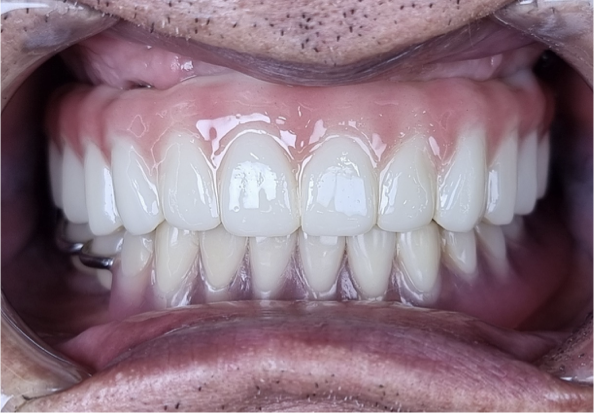

치아, 잇몸의 건강상태에 대해 충분한 설명을 듣고 치료기간, 비용, 보장기간 등을 고려하여 치료에 신중을 기해야합니다. 바른이치 치과는 임플란트 수술 후 잇몸염증이나 신경 제거와 같은 철저한 사후관리를 약속드립니다.

정직한 진단과 최소한의 수술

무조건 기존 임플란트를 제거하기 보다

잇몸염증 치료 후 가능하면 기존 임플란트를 살리려 노력합니다.

근본적인 원인 제거와 철저한 사후 관리

피해 부작용이 가장 많이 나타나는

임플란트 주위의 염증을 잇몸치료를 통해 확실히 제거합니다.